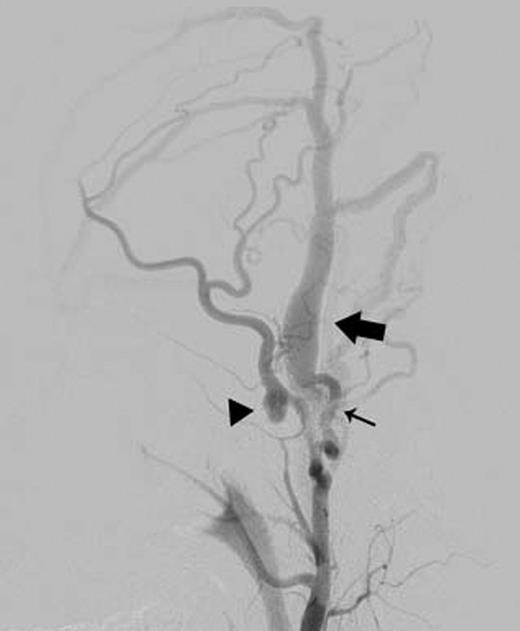

Left external carotid arteriography showed a high-flow AVF from the parietal branch of the STA (thin arrow) to the STV (wide arrow), and an aneurysm on the frontal branch of the STA (arrowhead).